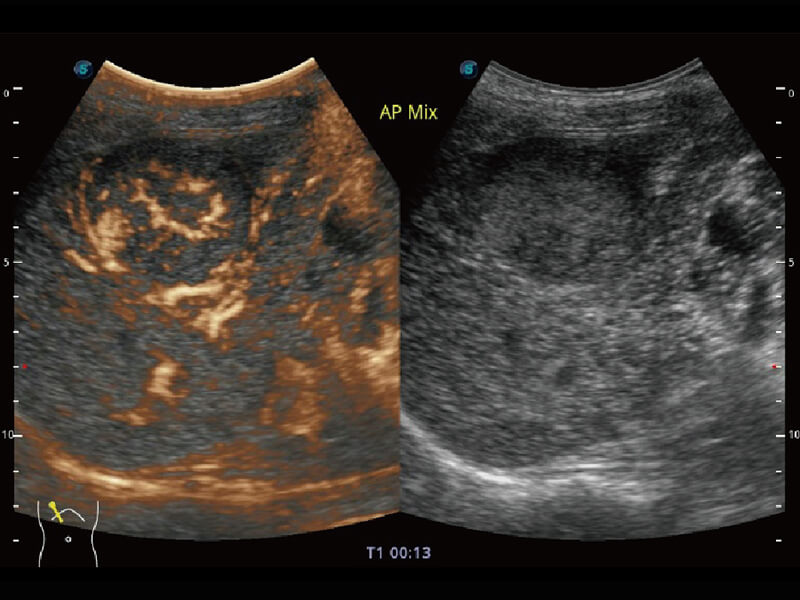

性能优异的硬件架构,极大提升超声系统的运行效率和数据处理能力。相比以往超声成像系统,Wis+平台为您带来极快的响应速度和成像帧频,提升检查流畅度。

S60探头工艺,从前端信号处理每一个环节采集无损声学数据,真实还原组织原貌,再现解剖细节。

超宽频带技术,为容积成像带来优质的二维图像基础,为您呈现丰富的结构细节,栩栩如生地展示宝宝的宫内形态以及各种组织的立体结构。